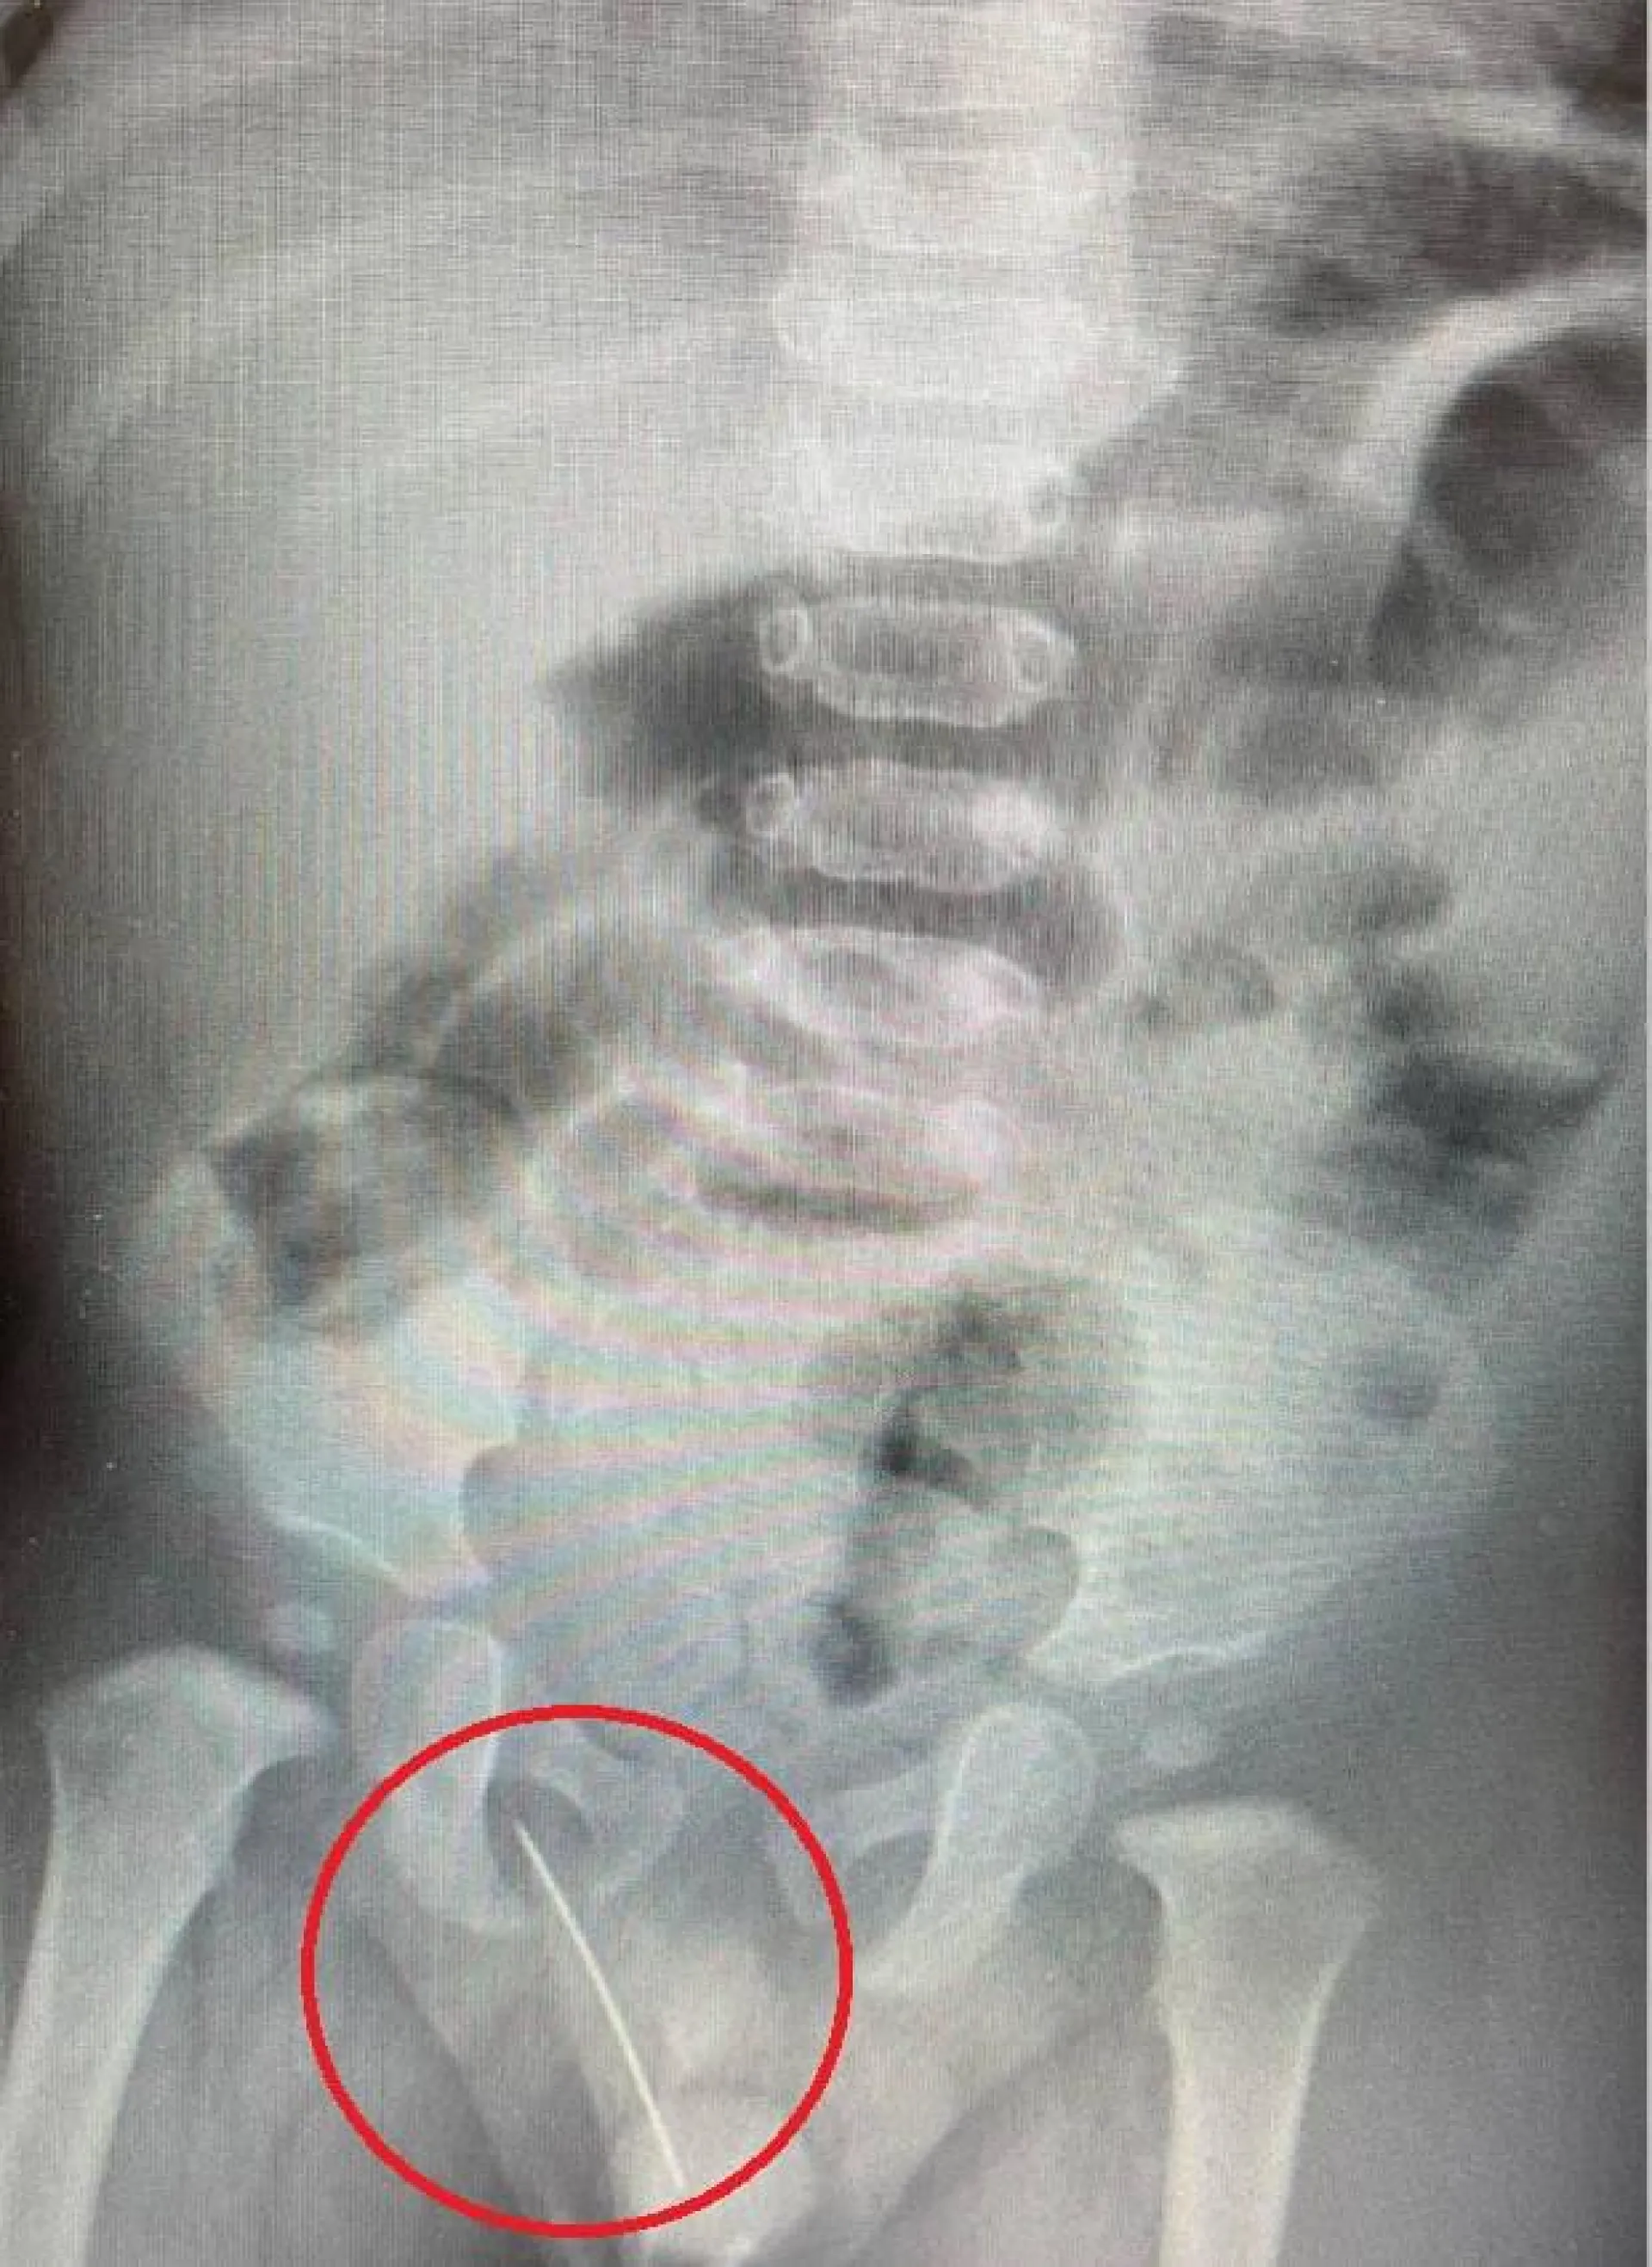

Швейную иглу извлекли из промежности годовалого россиянина

Бригада скорой помощи в Московской области доставила годовалого мальчика в детский научно-клинический центр Рошаля. У ребенка была выраженная боль в промежности, не позволявшая даже встать на ноги.

Рентген показал, что в мягких тканях между мошонкой и прямой кишкой пациента находится инородное тело. Это швейная игла, которая прошла в опасной близости от уретры.

«Мы выполнили ребенку экстренную операцию по извлечению инородного тела, после которой болевой синдром был полностью купирован. Операция прошла успешно, без осложнений», – рассказал завотделением детской хирургии №1 Евгений Рожденкин.

Как игла попала в тело ребенка? Медики полагают, что мальчик случайно сел на предмет.

К счастью, игла не навредила организму маленького пациента. Его выписали домой, сообщает областной Минздрав.